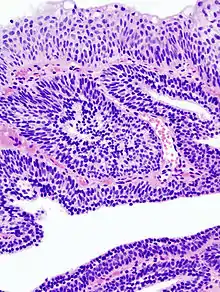

Photomicrographie d'un papillome malpighien sur une langue. Coloration à l'hématoxyline et à l'éosine.